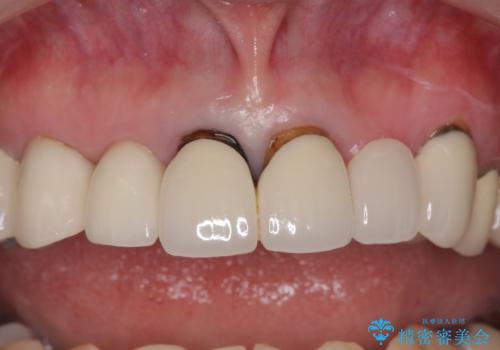

小さい前歯は、反対側と合わせた形にしました。

被せ物だけやりかえており、患者様のご希望もあり、根の治療や土台(コア)のやりかえは行なっていません。

- 25万円 内訳 左上23:ジルコニアクラウン(スペシャル)各10万円、仮歯 各1万円、オフィスホワイトニング(エクセレント)3万円費用は治療当時の料金となります

左右対称に仕上げることができ、治療には非常に満足していただきました。